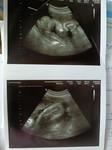

อายุครรภ์ 14w5d ปวดท้องน้อยส่วนล่างระหว่างขา ไม่มีเลือดออก ปกติไหมคะ เกิดจากอะไร🙏🏼